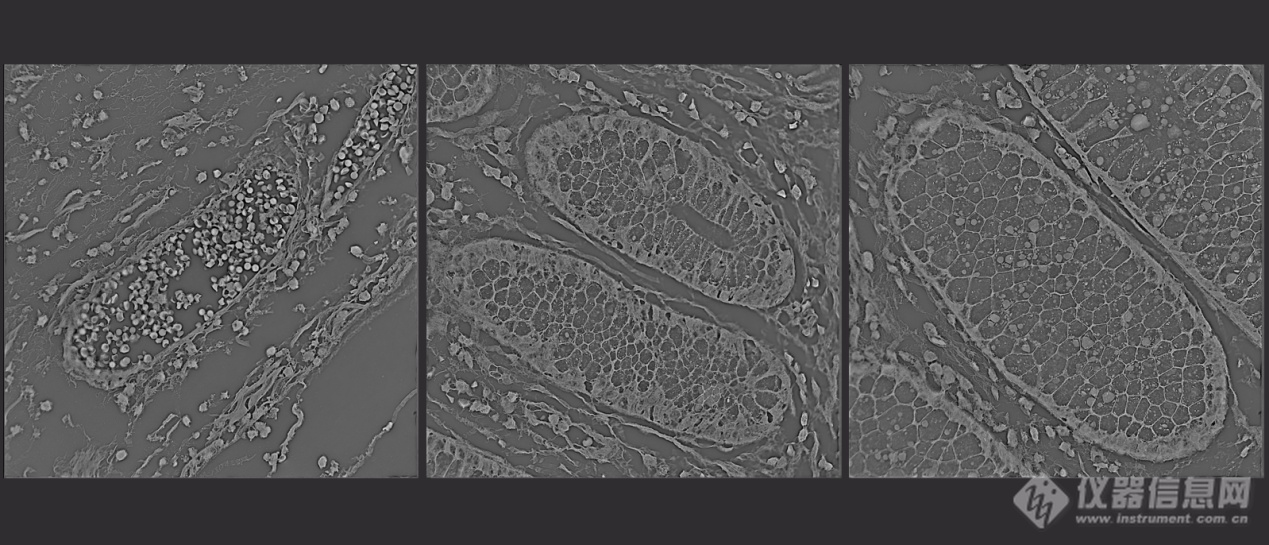

在菌类研究中,系统可观察菌体增殖、出芽等,实现对微生物行为的精准成像;在材料科学方面,系统可对材料的直径、折射率、圆度等进行直接观察与统计分析;此外,系统适用于组织切片及类器官成像,能够为组织病理学、类器官发育等研究提供高分辨、定量化数据。

图10 组织切片图光学衍射层析成像技术凭借其无标记、长时程、三维定量成像的独特优势,未来应用前景广阔。在基础科研领域,它将成为解析细胞生命周期、代谢动态、干细胞分化及细胞间相互作用的利器,特别是在类器官、肿瘤免疫等复杂模型研究中,能实现对细胞群体的原生态、高通量三维监测。其定量折射率参数更有望作为新的生物标志物。在临床与转化医学方面,该技术在无标记细胞病理学评估、辅助生殖中的胚胎质量动态筛查、以及药物高通量筛选等领域展现出巨大潜力,为疾病诊断与新药研发提供无损、客观的动态量化依据。